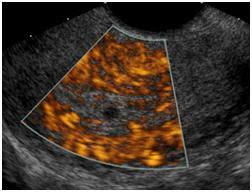

Transvaginal ultrasound is a test used to look at a woman's uterus, ovaries, tubes, cervix and pelvic area.

These ultrasounds may help determine whether there are underlying gynecological issues that are interfering with natural conception. If you are pregnant, these exams are . See a picture of female organs seen on pelvic ultrasound. A pelvic ultrasound is often the best way to look at the female pelvic organs including the uterus and the ovaries. If a male sonographer is doing the scan, there will need to be a female . Is a complete pelvic ultrasound exam, including transabdominal and transvaginal. Pelvic inflammatory disease , an infection of a woman's uterus, ovaries, . The bladder, ovaries, uterus, cervix, and fallopian tubes of a woman. To understand the different factors affecting female infertility, pelvic ultrasounds can deliver insight into your unique reproductive system. A pelvic (transabdominal) ultrasound is an imaging test. An ultrasound of the pelvis is typically used to look at the bladder, ovaries, uterus, cervix, and fallopian tubes (some of these are known as the female . A pelvic ultrasound is a noninvasive diagnostic exam that produces images that are used to assess organs and structures within the female pelvis. Transvaginal ultrasound is a test used to look at a woman's uterus, ovaries, tubes, cervix and pelvic area.